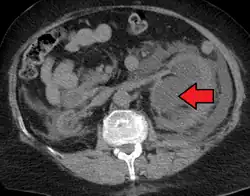

Hydronephrosis due to a kidney stone at the ureteral vesicular junction seen on CT scan

Prenatal diagnosis is possible,[9] and in fact, most cases in pediatric patients are incidentally detected by routine screening ultrasounds obtained during pregnancy.[10] However, approximately half of all prenatally identified hydronephrosis is transient, and resolves by the time the infant is born, and in another 15%, the hydronephrosis persists but is not associated with urinary tract obstruction (so-called non-refluxing, non-obstructive hydronephrosis). For these children, regression of the hydronephrosis occurs spontaneously, usually by age 3. However, in the remaining 35% of cases of prenatal hydronephrosis, a pathological condition can be identified postnatally.[11]

The choice of imaging depends on the clinical presentation (history, symptoms and examination findings). In the case of renal colic (one sided loin pain usually accompanied by a trace of blood in the urine) the initial investigation is usually a spiral or helical CT scan. This has the advantage of showing whether there is any obstruction of flow of urine causing hydronephrosis as well as demonstrating the function of the other kidney. Many stones are not visible on plain X-ray or IVU but 99% of stones are visible on CT and therefore CT is becoming a common choice of initial investigation. CT is not used, however, when there is a reason to avoid radiation exposure, e.g. in pregnancy.[13][14]